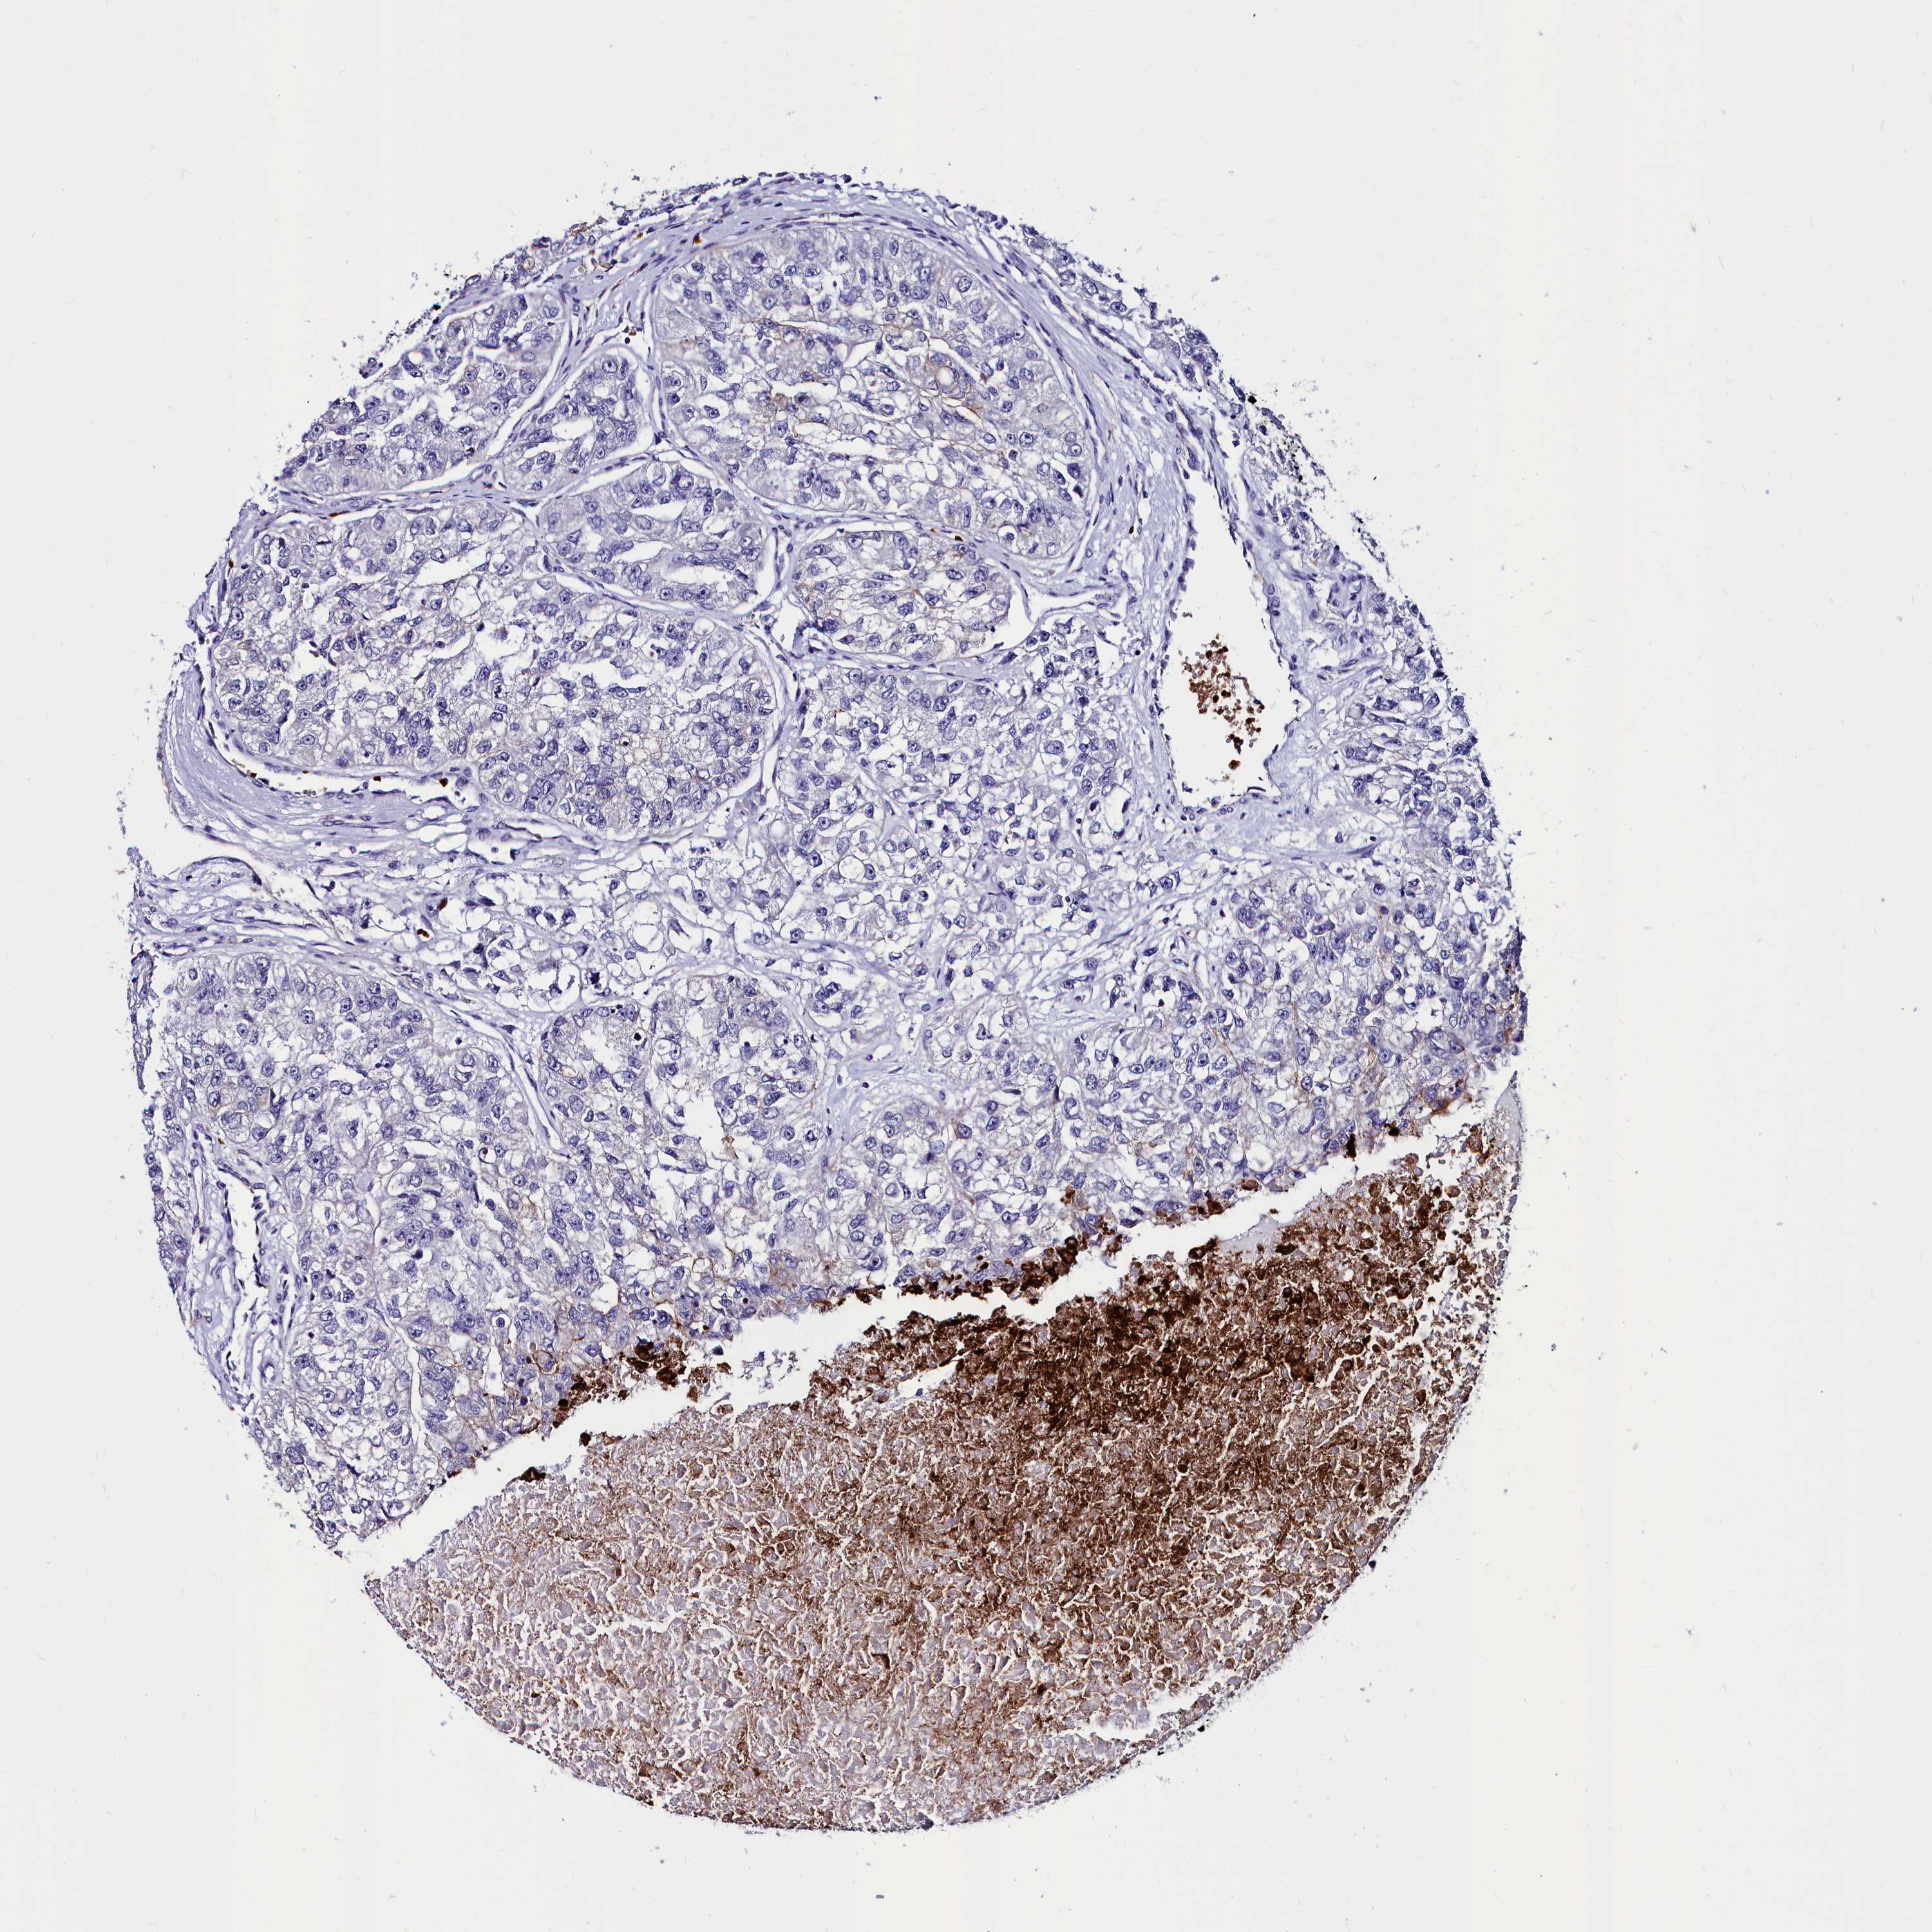

KIDNEY RENAL CLEAR CELL CARCINOMA (TCGA) - Interactive survival scatter ploti

The Survival Scatter plot shows the clinical status (i.e. dead or alive) for all individuals in the patient cohort, based on the same data that underlies the corresponding Kaplan-Meier plots. Patients that are alive at last time for follow-up are shown in blue and patients who have died during the study are shown in red.

The x-axis shows the expression levels (FPKM) of the investigated gene in the tumor tissue at the time of diagnosis. The y-axis shows the follow-up time after diagnosis (years). Both axes are complimented with kernel density curves demonstrating the data density over the axes. The top density plot shows the expression levels (FPKM) distribution among dead (red) and alive patients (blue). The right density plot shows the data density of the survived years of dead patients with high and low expression levels respectively, stratified using the cutoff indicated by the vertical dashed line through the Survival Scatter plot. This cutoff is automatically defined based on the FPKM cutoff that minimizes the p-score. The cutoff can be changed by dragging the vertical line or by entering a cutoff value in the square labeled "Current cut-off".

Under the Survival Scatter plot the p-score landscape (black curve; left axis) is shown together with dead median separation (red curve; right axis). Dead median separation is the difference in median mRNA expression between patients who have died with high and low expression, respectively. It is calculated as follows: median FPKM expression of dead patients with high expression - median FPKM expression of dead patients with low expression. This is intended to aid the user in visually exploring custom cutoffs and the associated p-scores and dead median separation.

Individual patient data is displayed and can be filtered by clicking on one or more of the category buttons on the top of the page. Categories describing expression level and patient information include: high, low, alive, dead, female, male and tumor stages. The scale of the x-axis can be toggled between linear and log-scale by clicking on the "x log" button. Mouse-over function shows TCGA ID, patient information and mRNA expression (FPKM) for each patient.

& Survival analysisi

Kaplan-Meier plots summarize results from analysis of correlation between mRNA expression level and patient survival. Patients were divided based on level of expression into one of the two groups "low" (under cut off) or "high" (over cut off). X-axis shows time for survival (years) and y-axis shows the probability of survival, where 1.0 corresponds to 100 percent.

CYP4F11 is not prognostic in Kidney Renal Clear Cell Carcinoma (TCGA)

Best expression cut offi

Based on the FPKM value of each gene, patients were classified into two groups and association between prognosis (survival) and gene expression (FPKM) was examined. The best expression cut-off refers the FPKM value that yields maximal difference with regard to survival between the two groups at the lowest log-rank P-value. Best expression cut-off was selected based on survival analysis .

When clicking on this number, the vertical dashed line indicating cut-off, the interactive survival plot, and the Kaplan-Meier curve will be adjusted to show results based on the best expression cut-off.

: 1.71

P scorei

Log-rank P value for Kaplan-Meier plot showing results from analysis of correlation between mRNA expression level and patient survival.

N/A

TCGA RNA samplesi

RNA-seq data is reported as average FPKM (number Fragments Per Kilobase of exon per Million reads), generated by the The Cancer Genome Atlas (TCGA) .

Normal distribution across the dataset is visualized with box plots, shown as median and 25th and 75th percentiles. Points are displayed as outliers if they are above or below 1.5 times the interquartile range. FPKM values of the individual samples are presented next to the box plot.

Average pTPM 3.6

Number of samples 521